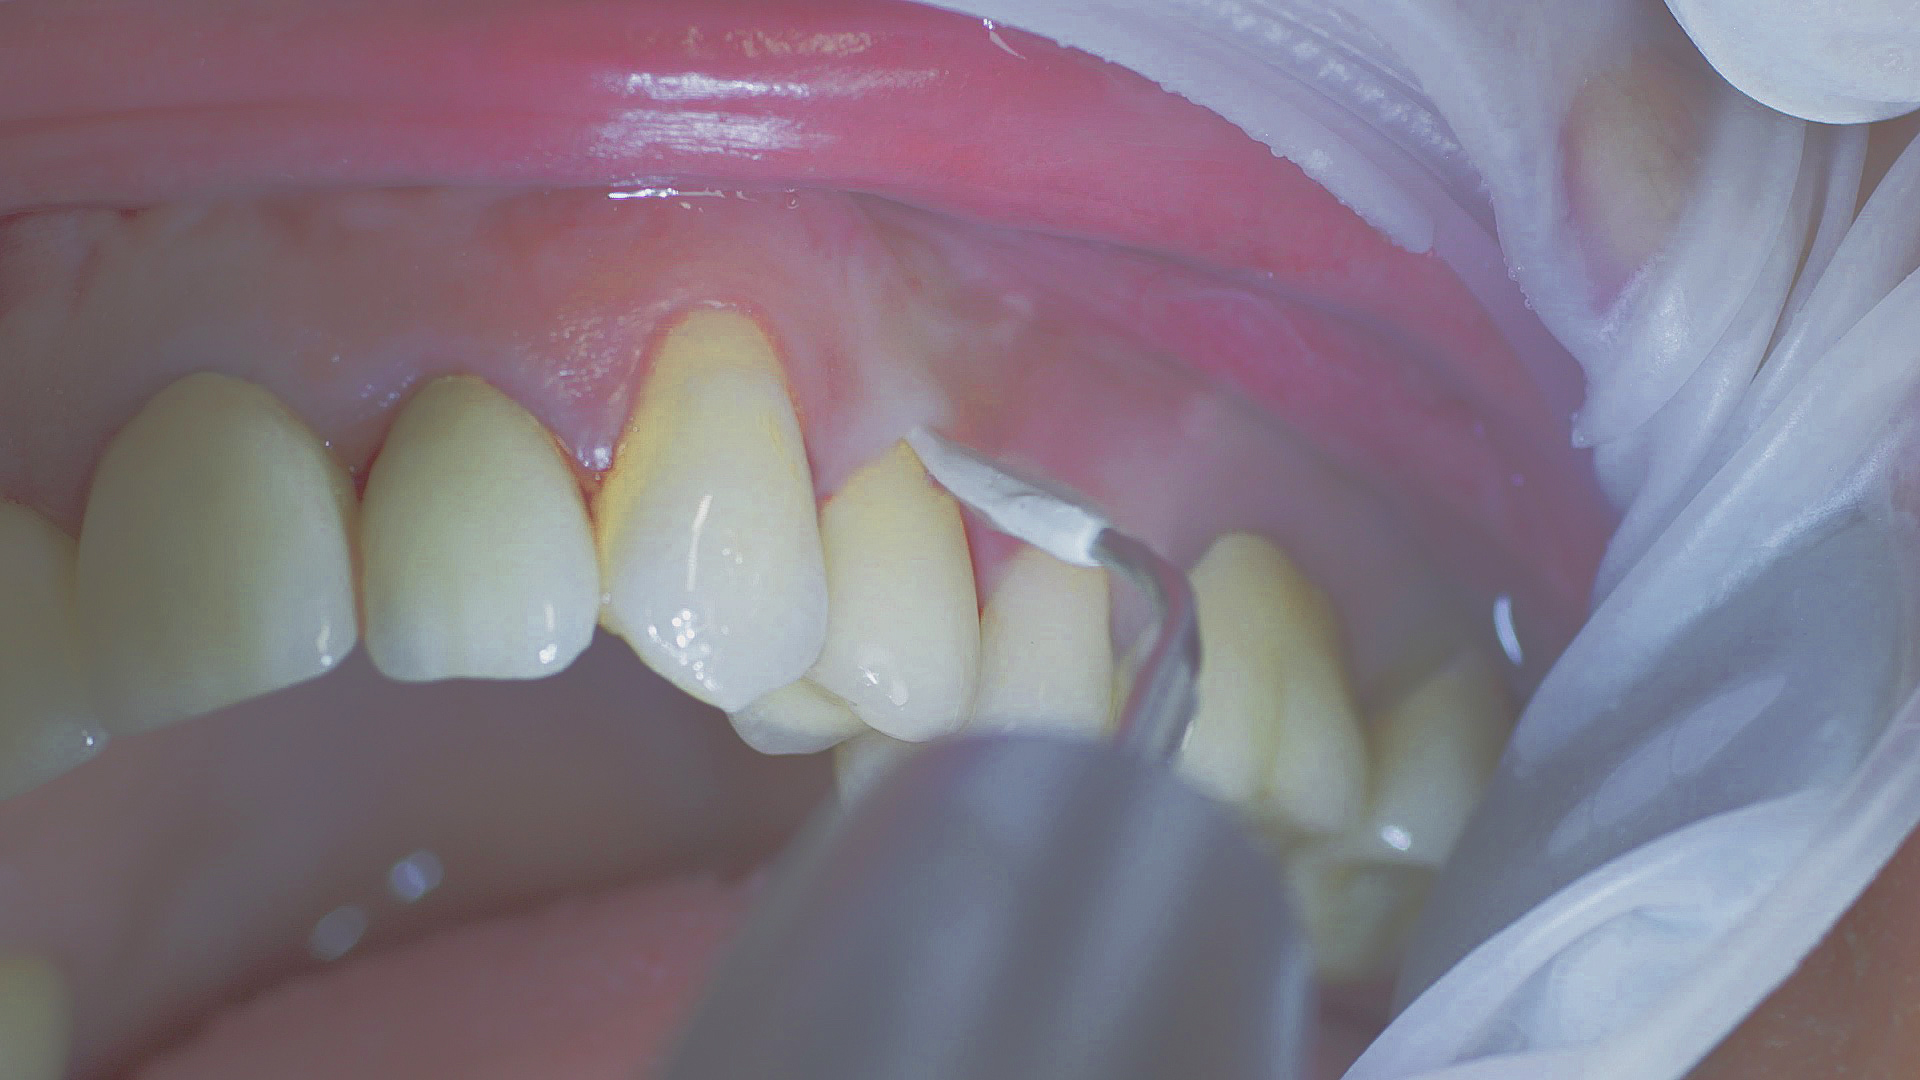

Every dental examination is based on a detailed medical history combined with targeted diagnostics con- taining as much detail as possible: The dentist records systemic risk factors such as diabetes or smoking and identifies any potential increased tendency to inflammation.[3] Hard and soft tissues are examined and periodontal pockets are probed in a screening test according to PSR (Periodontal Screening and Recording). In case of abnormal findings, the periodontal status is then re- corded and therapy is initiated where necessary. This treatment begins with professional biofilm management, by using, for example, rotary cups and polishing com pounds (Fig. 1), and comprehensive instructions in oral hygiene. Sonic or ultrasonic systems remain an effective alternative or supplement to manual instruments for sub- gingival debridement and biofilm management (presentation by Prof. Dr Ulrich Schlagenhauf; Fig. 2). Supplementary use of photodynamic therapy, air polishing or local and systemic antibiotics is not adequately documented (Prof. Dr Sema Hakki).[4] According to Dr Sergio Bizzarro, improved biomarker diagnostics may lead to an increase in customised patient therapy in the future.

Fig. 1: Good individual oral hygiene and professional biofilm management, e.g. with cups and brushes, helps support periodontal and peri-implant health.